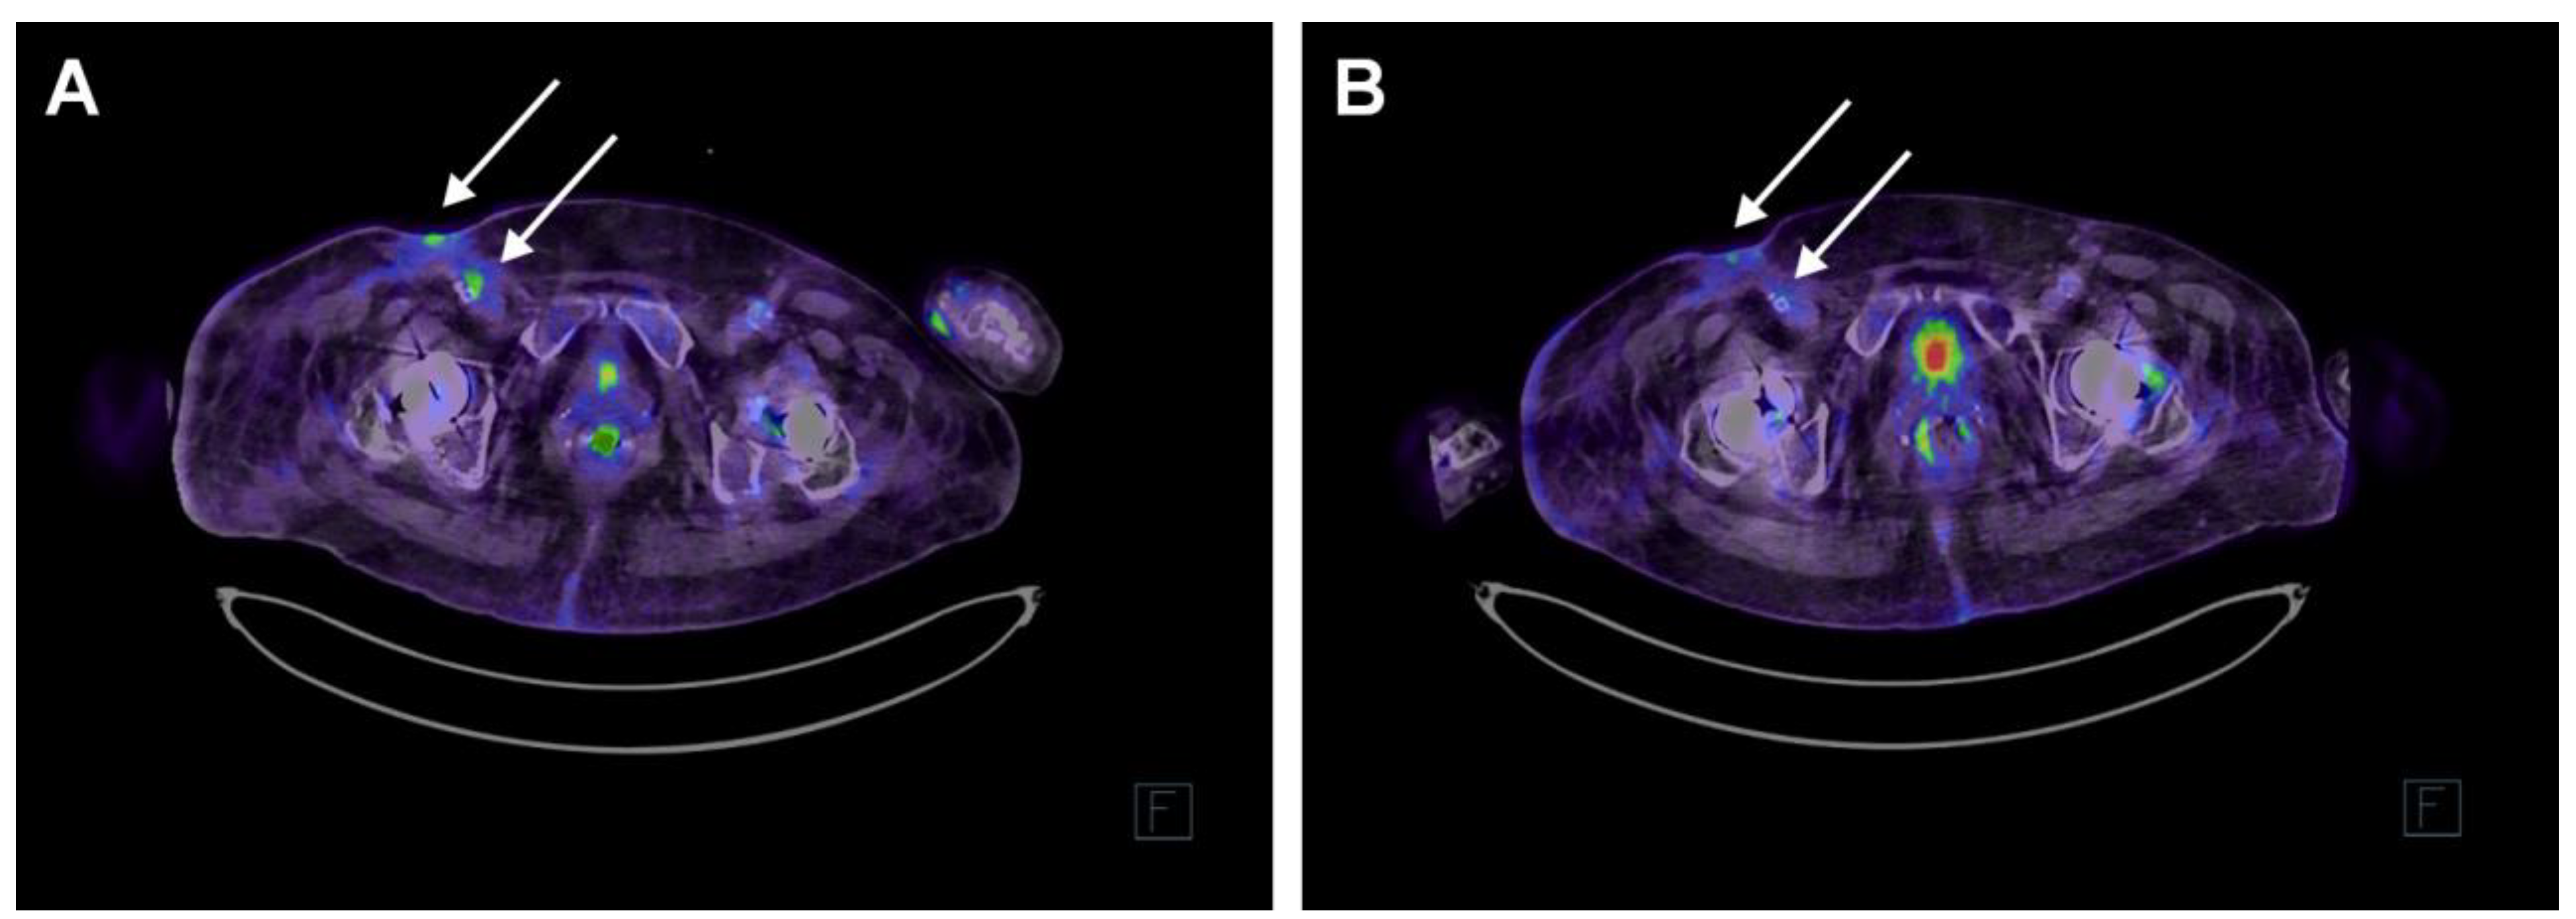

2. Case Report

2.3. Phage Treatment of the Patient